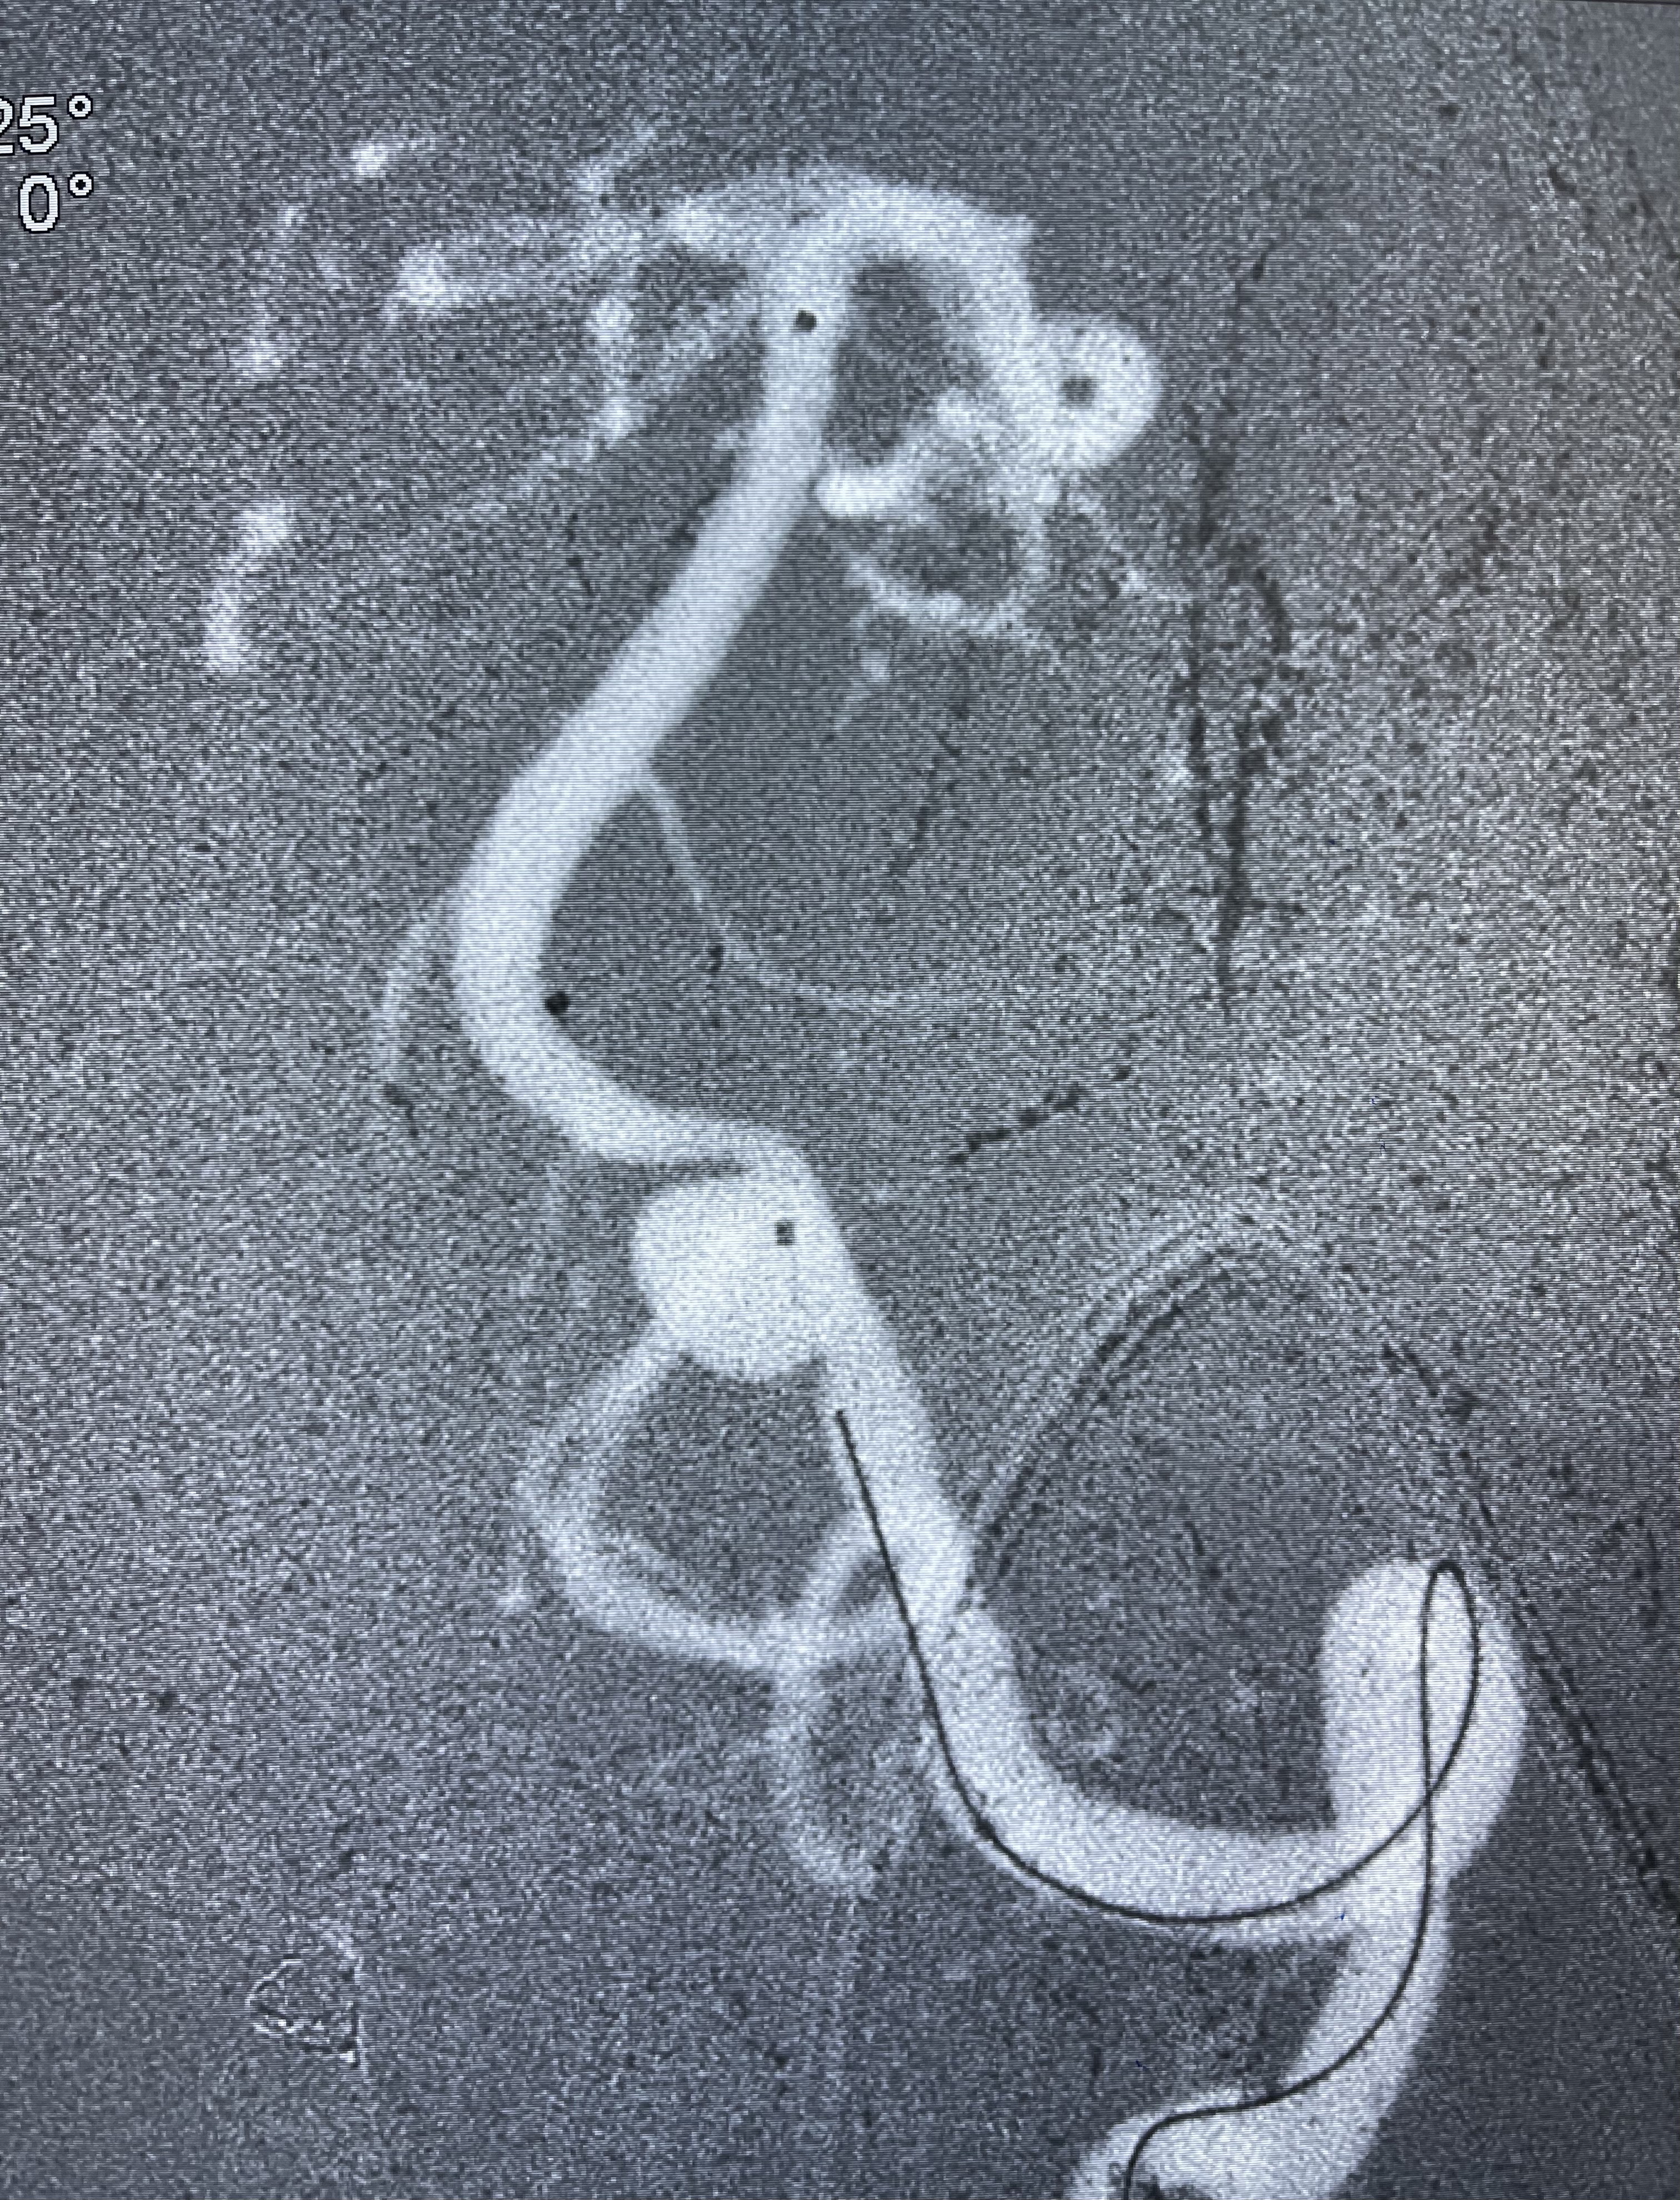

支架到位

支架释放,透视下